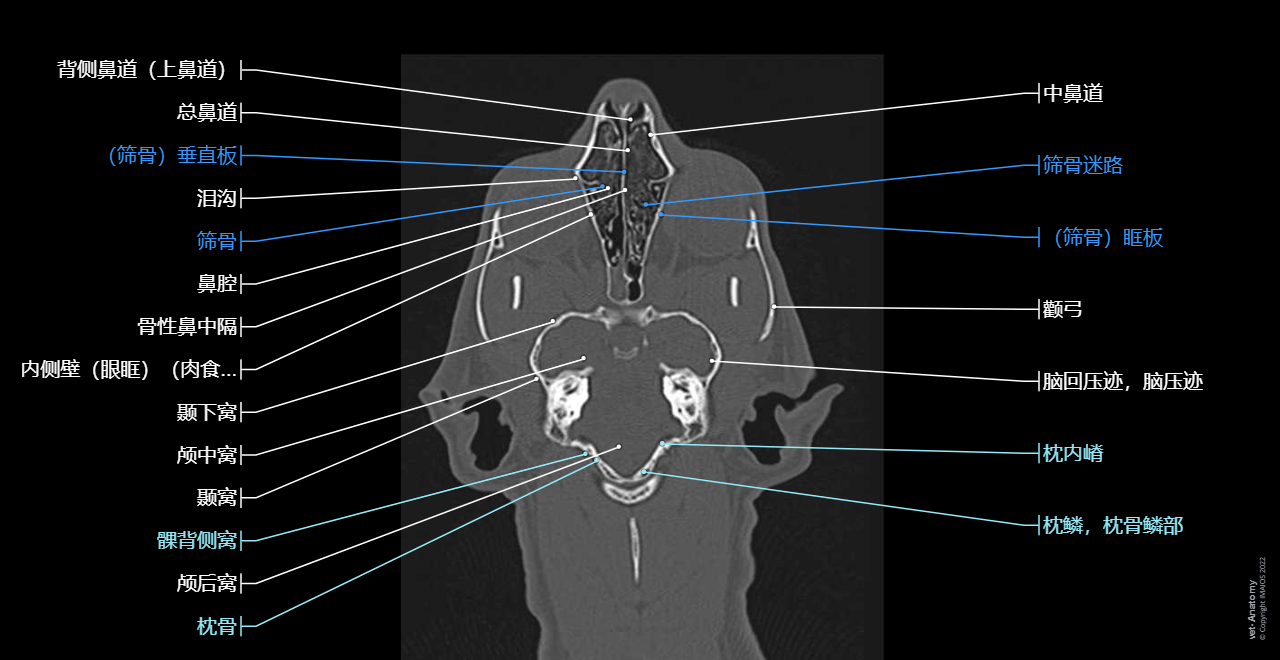

正常猫的头颈部CT解剖

- Antoine MICHEAU, MD , Denis HOA, MD , Susanne AEB Boroffka, PhD - dipl. ECVDI

- 发布日期: 2019年10月11日 | 最新更新 2025年3月18日